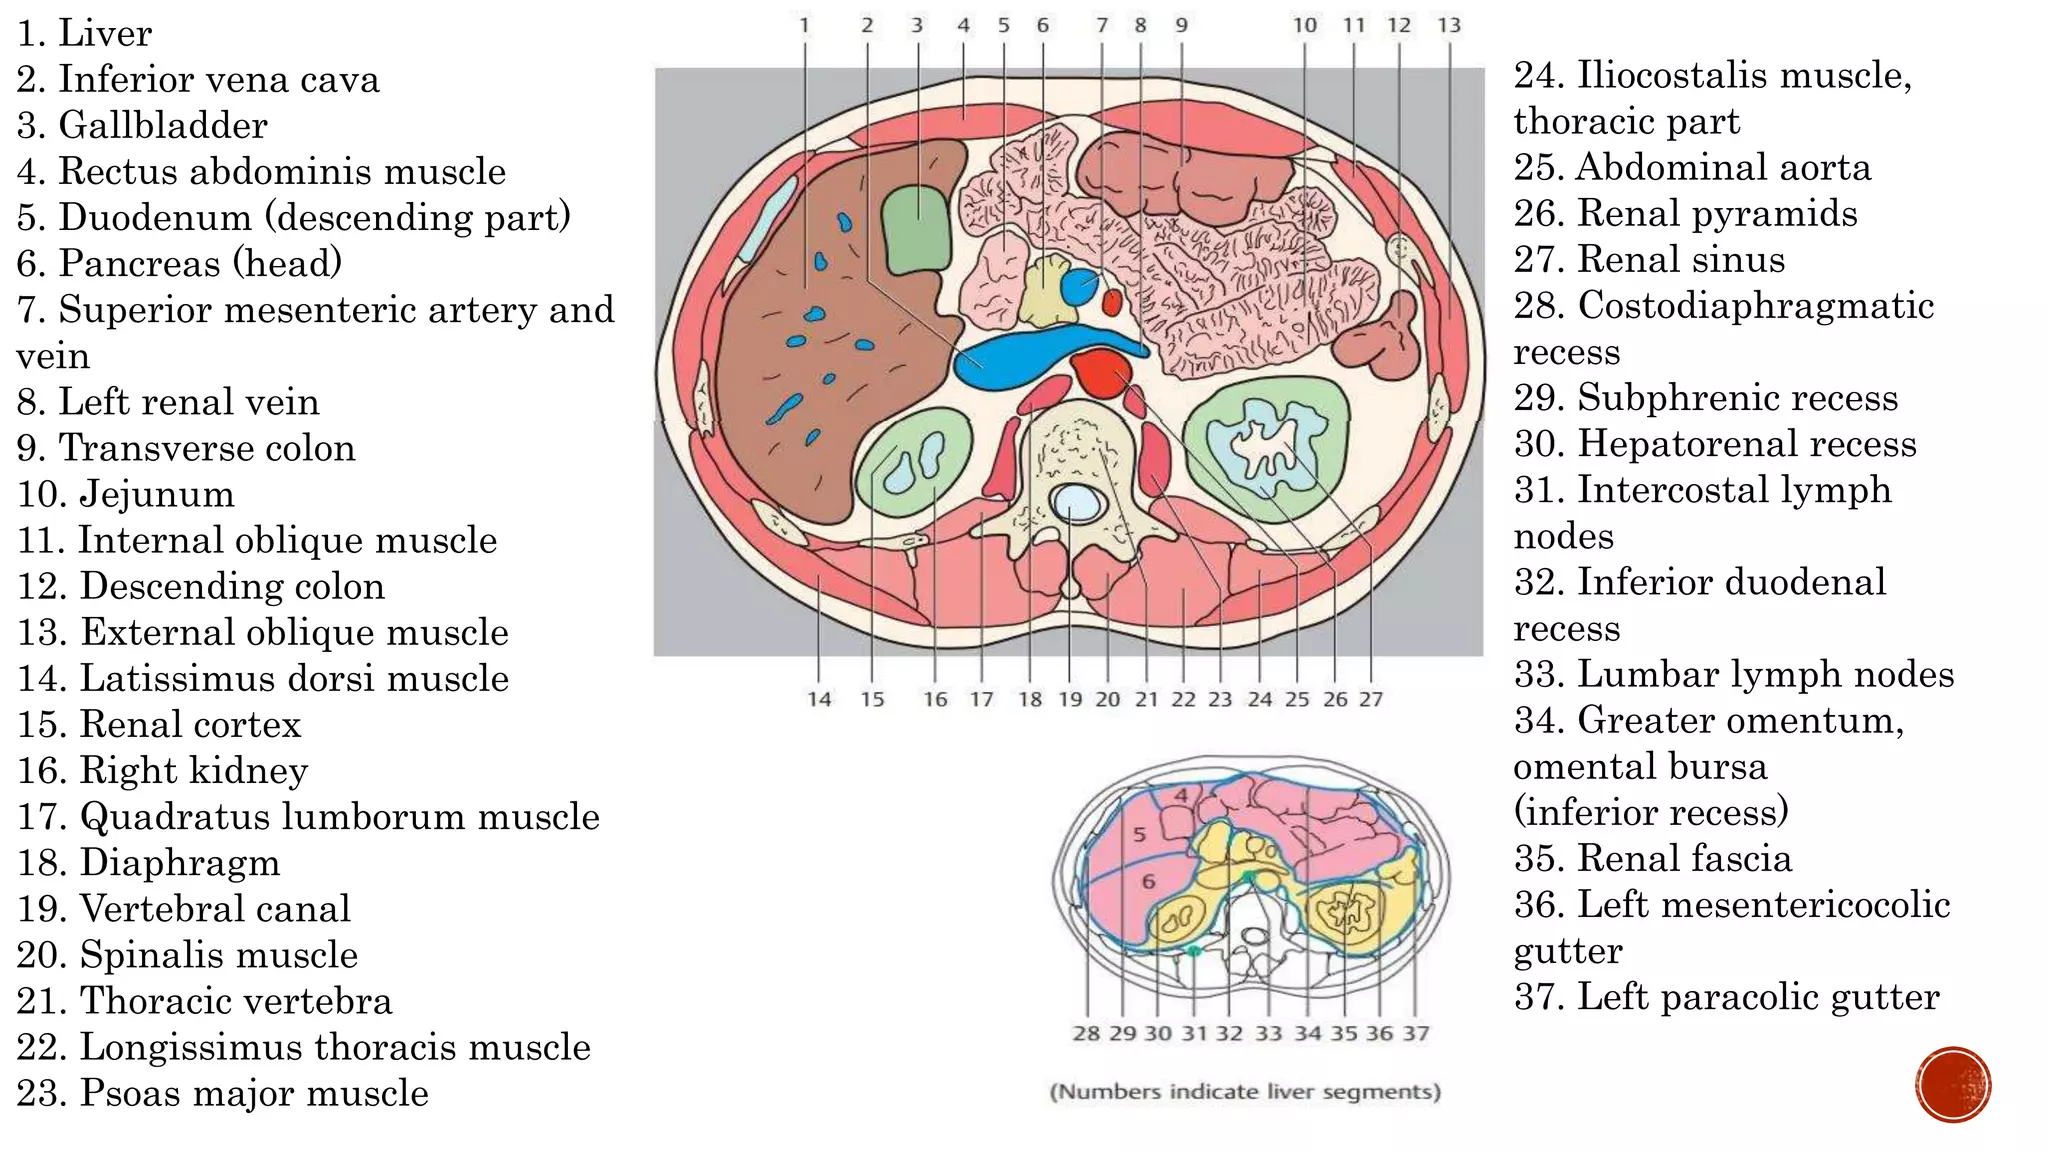

The document describes the anatomy of the abdomen and pelvis region of the human body. It lists over 40 structures and their locations, including major organs like the liver, kidneys, intestines, blood vessels and muscles of the abdominal wall and pelvis. The structures are grouped into sections focusing on different anatomical areas like the abdomen, retroperitoneum, pelvis and gluteal region.